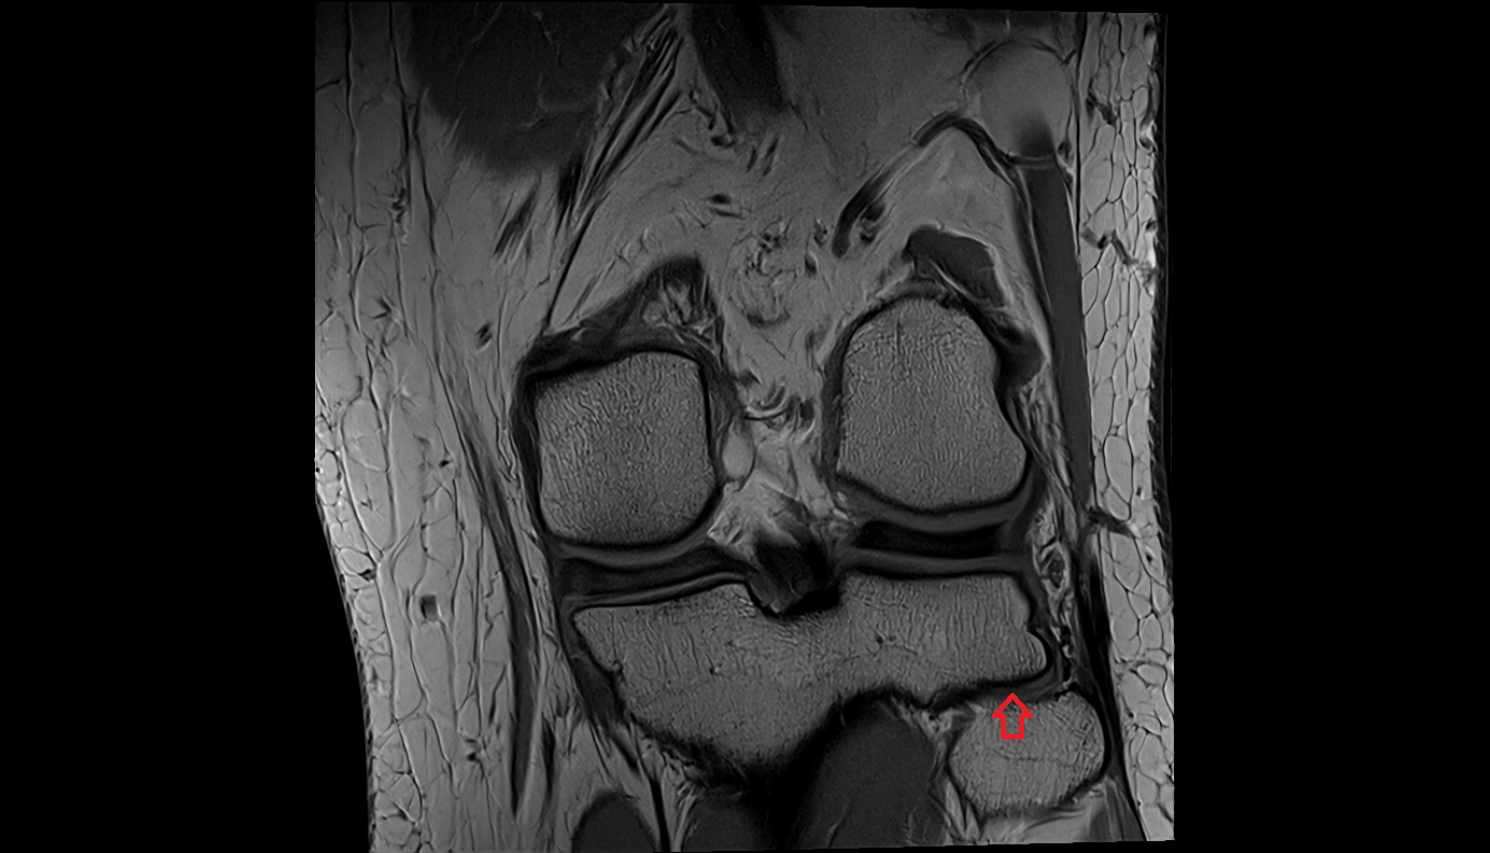

- Elbow joint

- Medial collateral ligament complex of elbow (ulnar collateral ligament)

- Medial collateral ligament of elbow (anterior bundle)

- Medial collateral ligament of elbow (posterior bundle)

- Medial epicondyle of humerus